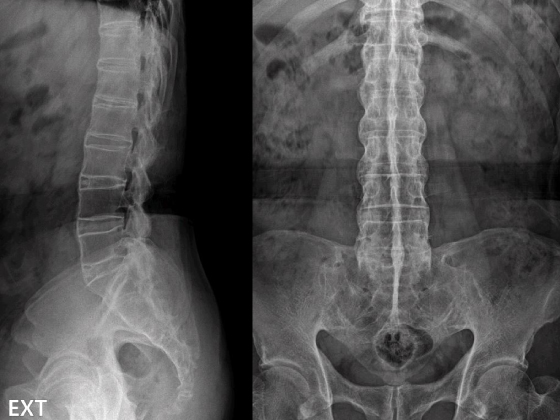

단순 X-ray 천장관절염

엑스레이(X-ray)

진행된 천장관절염을 확인할 수 있습니다.